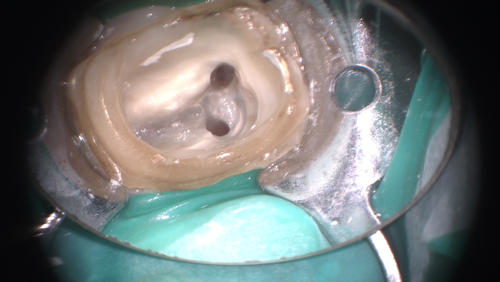

削り出したセラミックにグレーズという処理を行って模型に戻したところ。適合検査はブルーシリコーンで行います。横から見ると隣接面のトリミングがよく見えます。